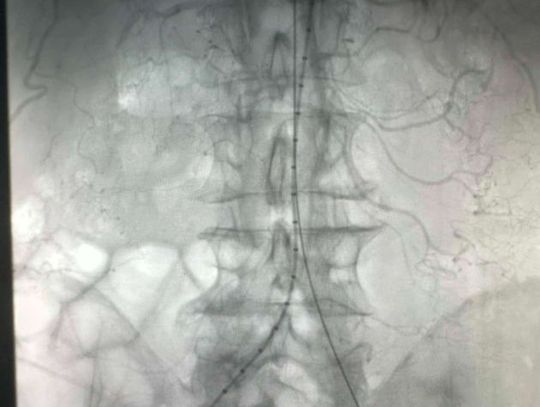

Takie operacje nie są codziennością, a wykonuje się je głównie w klinikach - i to dopiero od pięciu lat. W ostatnim czasie lekarze z Mazowieckiego Szpitala Specjalistycznego w Radomiu skutecznie udrożnili aortę podnerkową metodą wewnątrznaczyniową. - Pacjent mógł stracić nie tylko obie kończyny dolne, ale również i życie. Tutaj akurat wybraliśmy tę metodę, ponieważ ona była najbardziej adekwatna. Pacjent miał najwyższe szanse, żeby tę operację przeżyć i najwyższe szanse, żeby później po tej operacji przejść przez okres rekonwalescencji - tłumaczy lek. Renata Florek Szymańska, kierowniczka oddziału chirurgii naczyniowej w MSS.

Dzięki małoinwazyjnej metodzie wewnątrznaczyniowej nie jest konieczne otwieranie jamy brzusznej. - Było to nie tylko korzystniejsze dla zdrowia pacjenta, ale również i dla nas, chirurgów naczyniowych. Operacja trwała zdecydowanie krócej niż ta klasyczna. Polegała na wyłonieniu tętnic w pachwinach, co wiązało się też z mniejszymi ranami pooperacyjnymi - mówi Florek Szymańska.